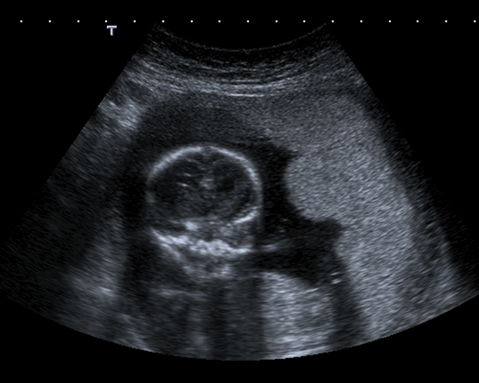

This image shows a lateral placenta. Notice how the placenta may have lobulated margins but still the same mid range echoes. On this transverse scan, the placenta is on the side wall of the uterus.